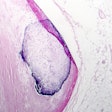

![]() |

| All images courtesy of Dr. Jean-Louis Sablayrolles. |